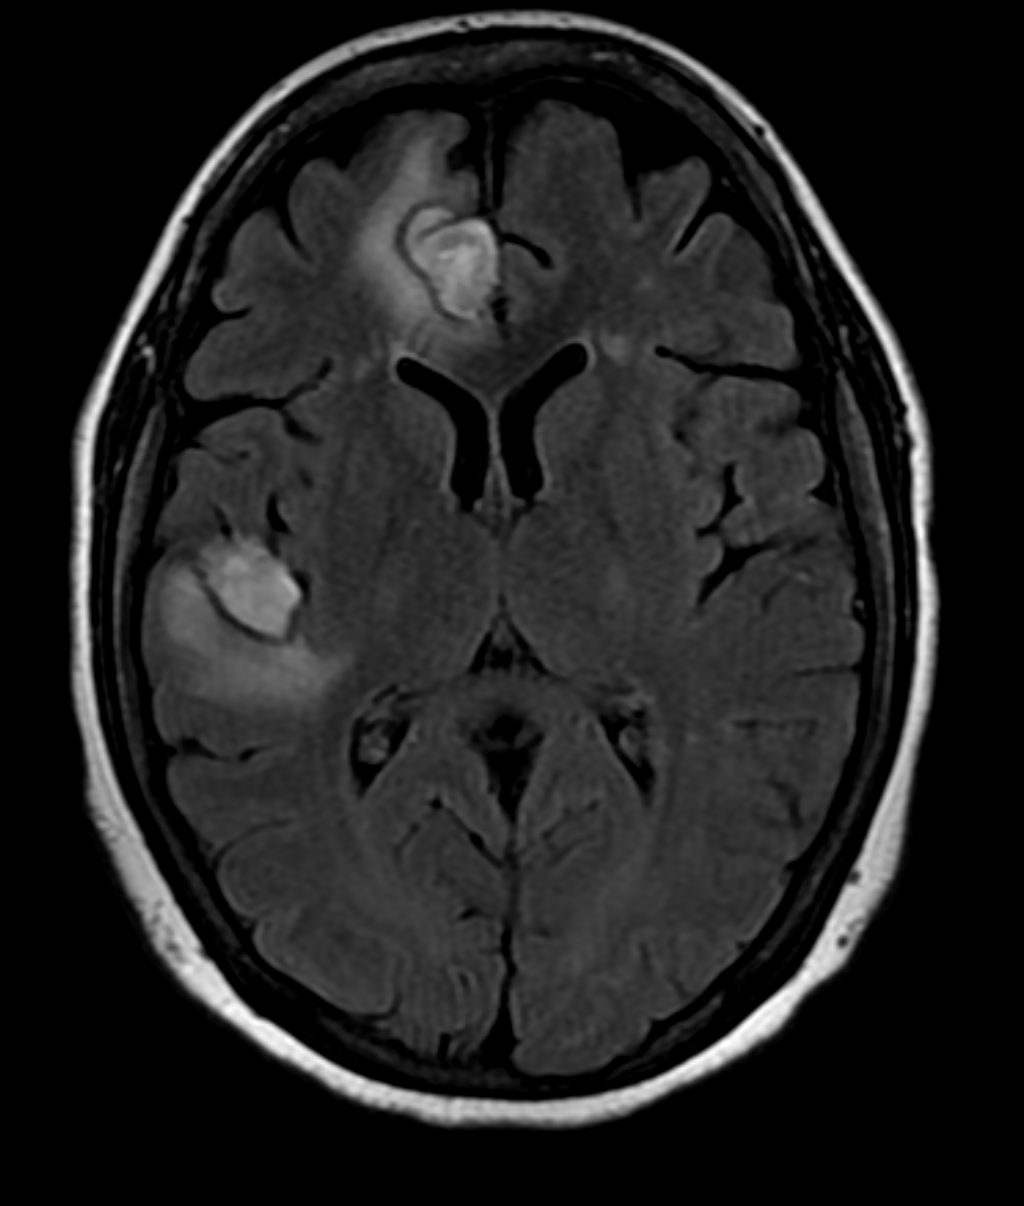

Case Presentation: : A 34-year-old female with history of migrainous headaches presented with complains of sudden onset, throbbing type of headache radiating to the back of the ear. This was associated with sudden loss of vision in the right eye. She also mentioned night sweats and unintentional weight loss in the last couple of months. She was diagnosed with grade 1 neuroendocrine tumor three months ago. On examination, she exhibited tenderness over the right temporal area and a decrease in visual acuity on the right eye. She did not show any signs of other focal neurological deficits. Initial laboratory investigations revealed thrombocytopenia and an elevated erythrocyte sediment rate. She was empirically treated with high dose glucocorticoids. Computed tomography (CT) scan of brain without contrast did not show evidence of intracranial hemorrhage. However, there were low density areas in the right frontal and temporal lobes suggesting possible demyelinating diseases, infarcts or metastasis. The patient was treated with high dose prednisone, which improved her visual acuity. This led us to do bilateral temporal artery biopsy which was negative for temporal arteritis. Magnetic resonance imaging (MRI) of the brain showed hemorrhagic areas which suggested the possibility of hemorrhagic intracranial metastatic disease, septic emboli or CNS vasculitis. Septic embolism was a distinct consideration, though this was excluded by negative transthoracic echocardiogram and blood cultures. The incidence of metastatic grade 1 neuroendocrine tumor is rare and seemed unlikely. We then proceeded to evaluate for vasculitis. Anti-nuclear antibody titers were highly positive as was Anti- double stranded DNA antibody. Complement 3 and 4 were low. Her presentation was consistent with SLE. On the next step, MR angiogram of brain confirmed small vessel hemorrhage in the right frontotemporal lobe suggestive of CNS vasculitis. High dose prednisone was continued for two weeks and a follow up MRI of brain showed improvement in the hemorrhagic areas. We concluded that the patient was suffering from CNS vasculitis secondary to SLE.